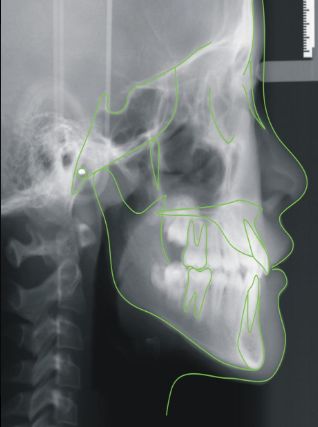

成年人正畸治疗后效果:↓